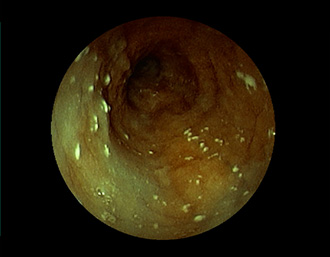

胃潰瘍(Stage S1)・・治療後5ヶ月

潰瘍の中心に白苔はなく、わずかに陥凹する潰瘍面に発赤が残る再生上皮が覆い尽くす(赤色瘢痕)。集中皺襞がなだらかに中心に延びている。→ ヘリコバクター・ピロリ感染を認めたため、除菌治療で駆除しました。